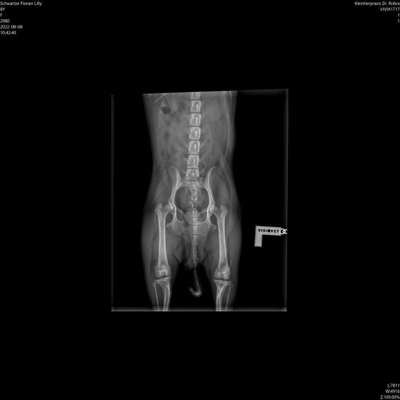

Hallo, Vorgestern ist mir beim Spaziergang aufgefallen, dass mein Hund eines der hinteren Pfötchen ganz komisch benutzt. Der Ballen ist wie verschoben und so wie auf dem Bild zu sehen läuft sie auch. Wenn sie stehenbleibt, nimmt sie es kurz hochband stellt es wieder richtig ab. So wie es sein sollte. Schmerzen scheint sie dabei keine zu haben. Wir waren denselben Tag noch beim Tierarzt aber der konnte damit gar nichts anfangen. Im Stand ist das Verschieben der Ballen bei beiden hinteren Pfötchen möglich. Bei meiner anderen Hündin jedoch nicht. Es handelt sich um einen Chihuahua Zwergpinscher Mischling und sie ist knapp 9Jahre. Sie ist kastriert und läuft gerne mega viel. Sie wiegt 2,2kg. Gestern und heute ist mir aufgefallen, dass sie im Wald länger normal geht aber sobald wir auf Asphalt unterwegs sind, passiert es wieder dass sie so anders mit dem Pfötchen geht. Ich weiß nicht was ich machen soll und möchte ihr so gerne helfen. Über jede Antwort und Hilfestellung bin ich sehr sehr dankbar! Lieben Gruß Janine mit Lilly

Ich kann Ihnen da leider nicht sagen was da genau los ist aber ich vermute etwas mit den Bändern. Um das aber richtig aufzuklären wäre es ratsam mal bei einem Orthopäden vorstellig zu werden. Der könnte da vllt ein wenig Licht ins dunkle bringen. Von außen ohne Bildgebende Verfahren wäre alles nur Spekulation.